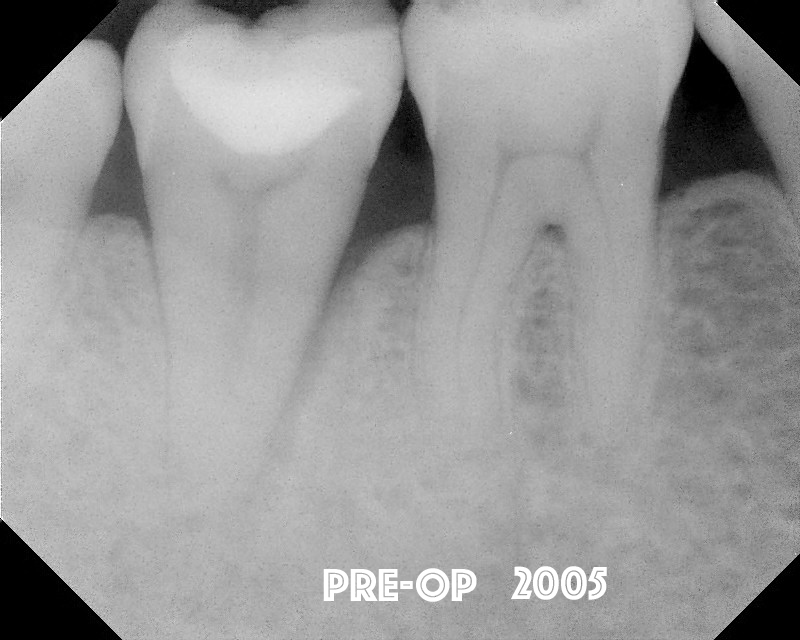

This most recent case is a periodontist who came to our practice.  I originally did the root canal in 2005.  It had an odd lateral lucency - which might be suggestive of a root fracture.  We completed root canal without finding a fracture.